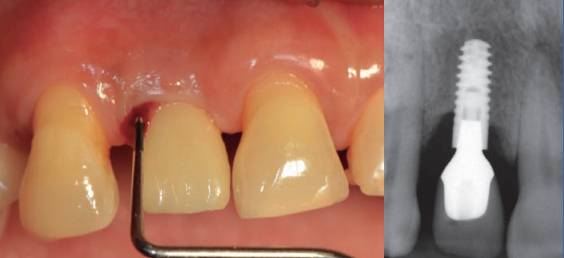

Tratamiento de enfermedades periimplantarias

Se refiere a la atención y manejo de enfermedades que afectan los tejidos alrededor de los implantes dentales, como la mucositis y la periimplantitis.

Manejo de mucositis periimplantaria

Se trata de la inflamación de los tejidos alrededor de un implante dental sin pérdida ósea significativa. Incluye limpieza y cuidado para evitar que la inflamación progrese a periimplantitis.

Tratamiento de periimplantitis

Es una infección que afecta los tejidos alrededor de un implante dental, causando pérdida ósea y posible fracaso del implante. El tratamiento incluye limpieza profunda y, en algunos casos, cirugía.

Mantenimiento de implantes dentales

Consiste en el seguimiento regular de los implantes dentales para asegurar su funcionamiento adecuado y prevenir problemas como la mucositis o la periimplantitis.